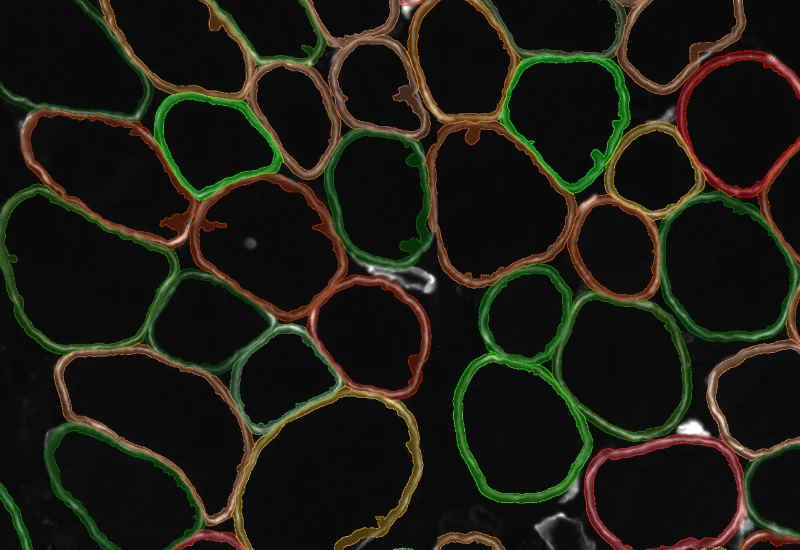

The IF Skeletal Muscle App allows the segmentation of skeletal muscle tissue sections into muscle fibres and connective tissue based on specific IF staining. As outcome parameters are provided such as number of muscle fibres, area of the total tissue, muscle fibres and connective tissue.

Segment IF-stained skeletal muscle into muscle fibers and connective tissue, and measure fiber count, total tissue area, muscle fiber area, and connective tissue area.